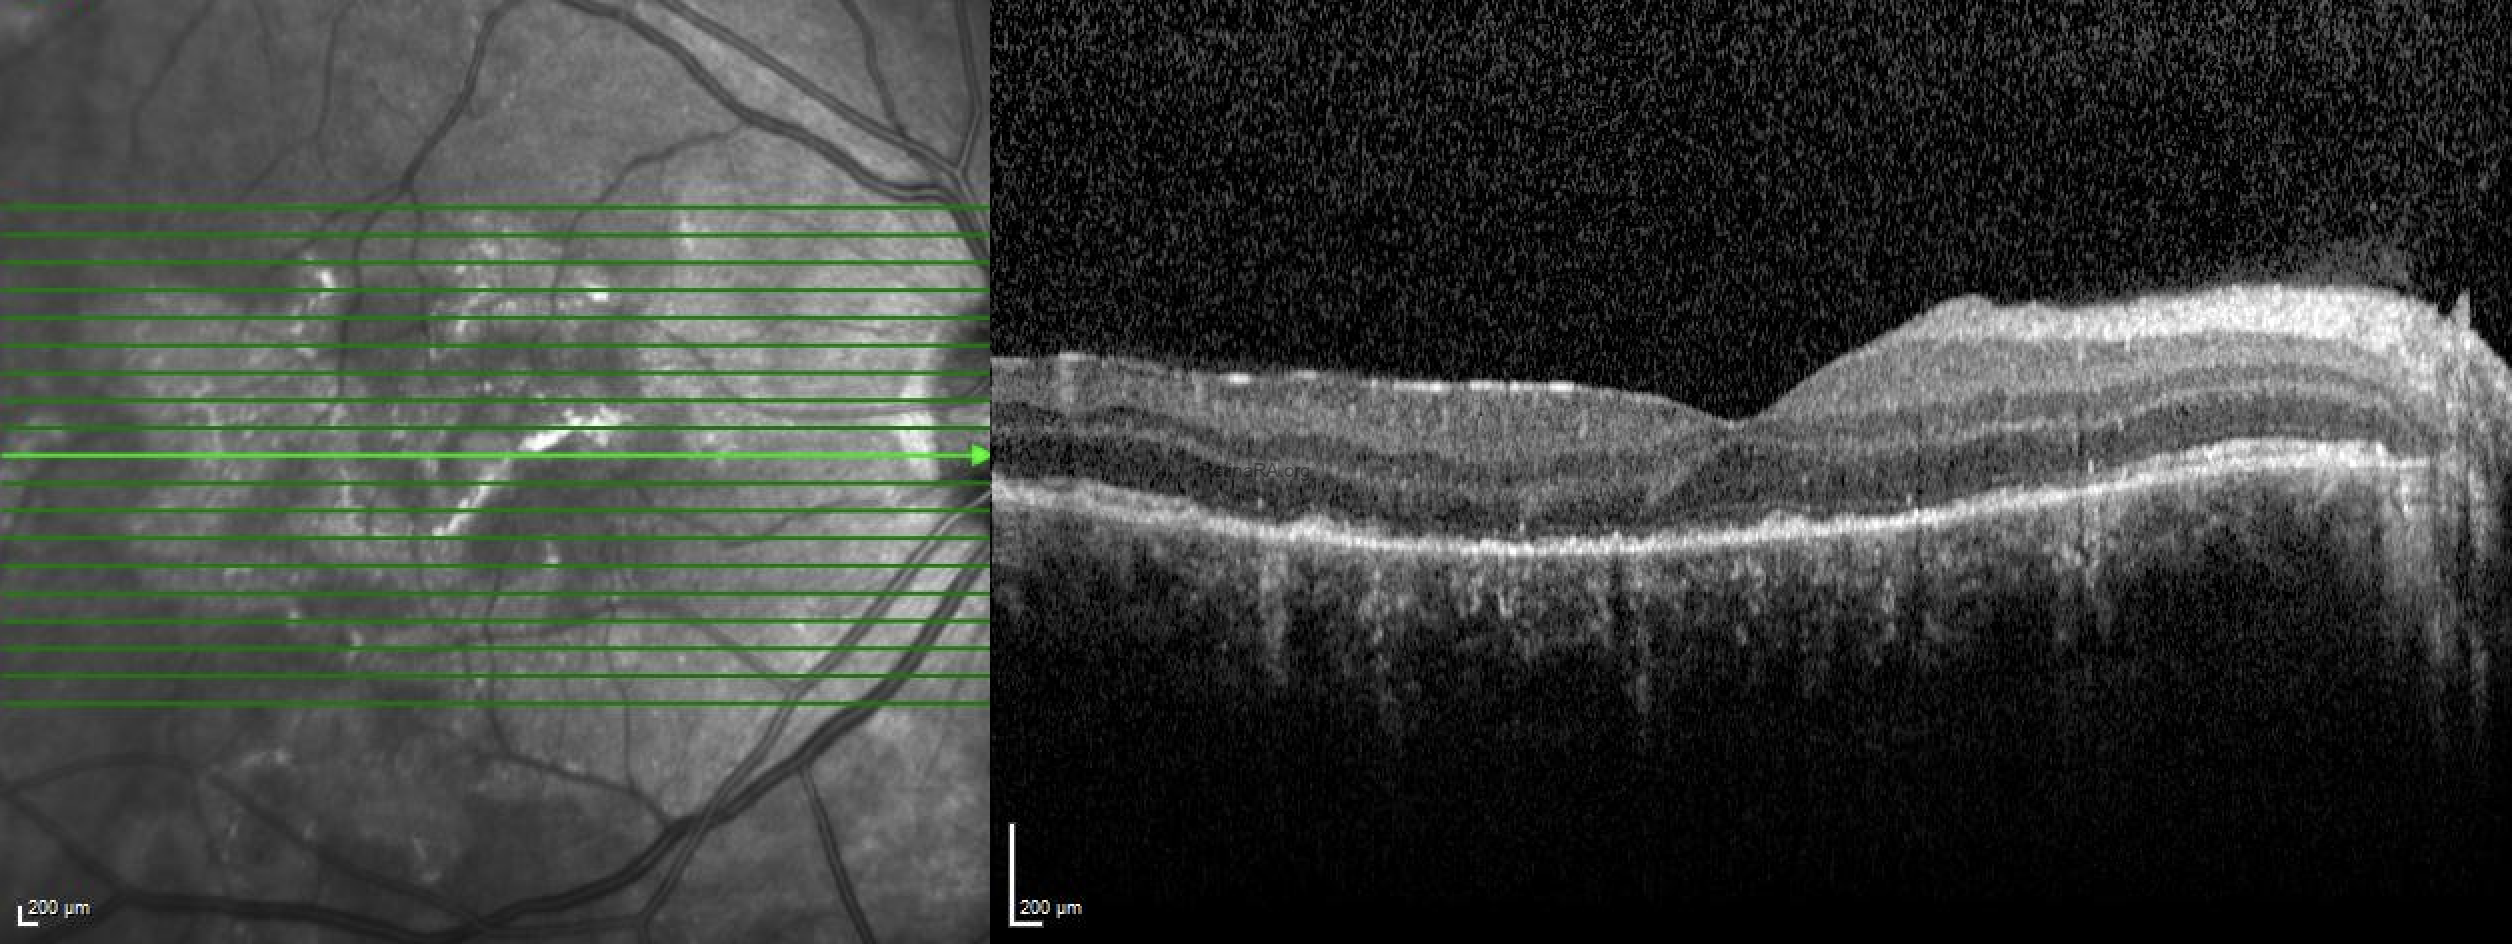

OCT sections show outer retinal atrophy and associated hyperreflectivity in the choroid.